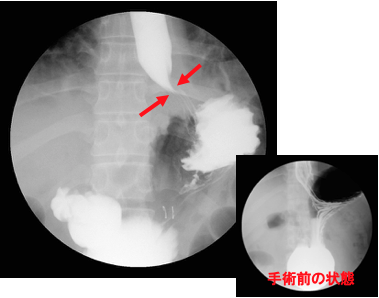

検査をすると、胃と食道の境目がゆるくて胃の一部が食道側に飛び出し(図1)、(図2)。一度胃に入ったバリウムが食道に戻ってきます(図3)。

検査中もバリウムが食道内へと逆流してきます。